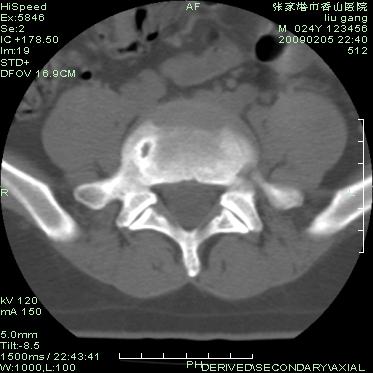

以下是引用随光逐影在2009-3-11 14:43:00的发言:[br]平片:l3、4、5及s1前上缘见类似“切角征”。[br]ct扫描:腰椎多个节段椎间盘向椎体内(椎体前部)突出。